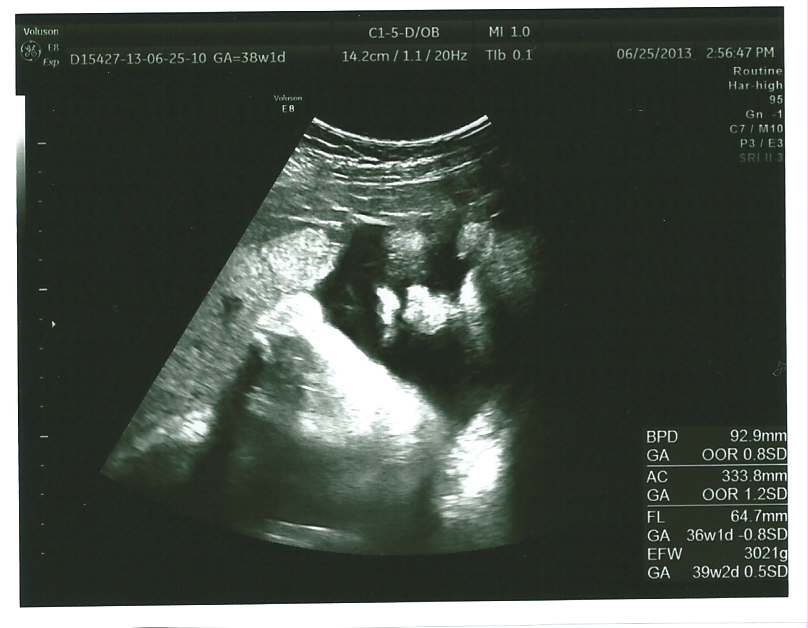

echo